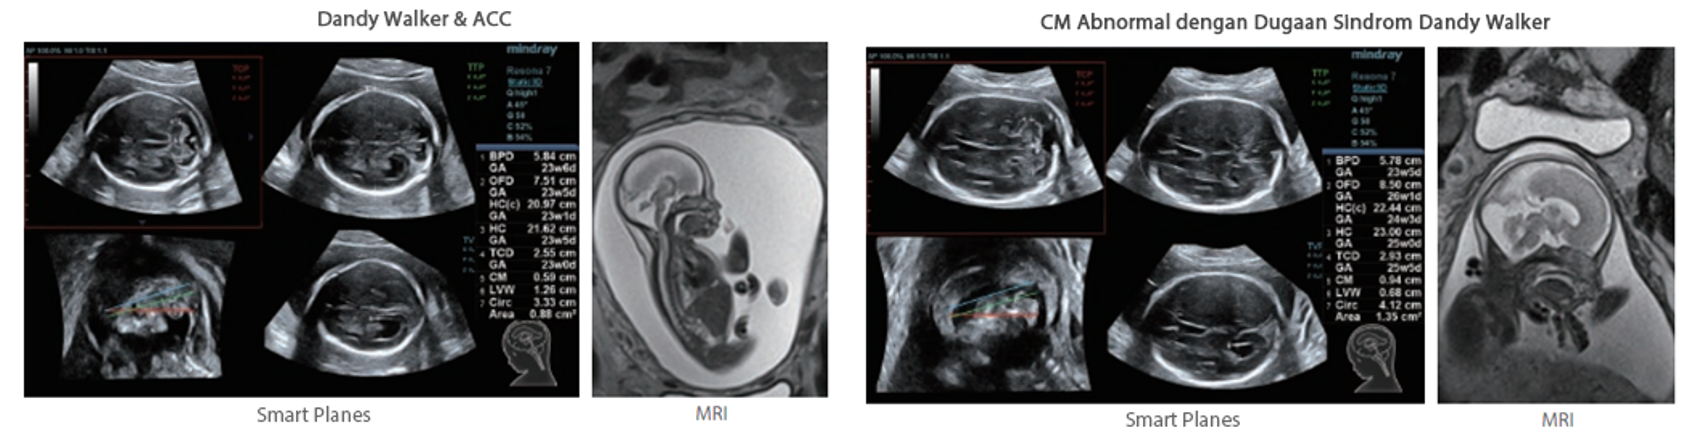

Selain kualitas gambar premium, Resona 7 juga meningkatkan kemampuan penelitian klinis dengan V Flow revolusioner untuk evaluasi hemodinamika vaskular, serta pengambilan penampang tercanggih dari rangkaian data 3D untuk diagnosis CNS pada janin. Kombinasi pengoperasian multisentuh berbasis gerakan yang paling intuitif dengan semua fitur klinis penting membuat Resona 7 menjadi gebrakan baru dalam inovasi ultrasound.